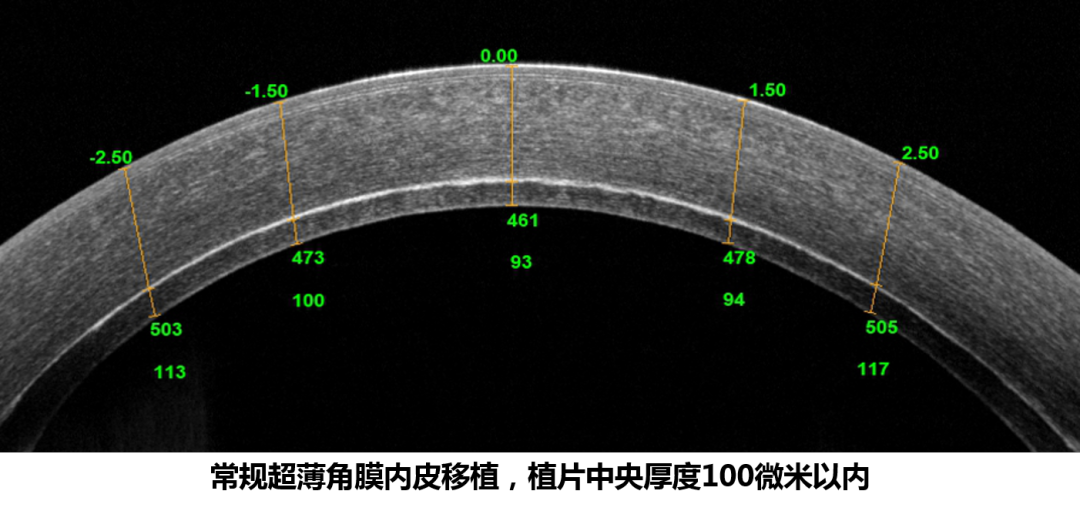

? ? ? 陳蔚教授介紹,“經(jīng)過我們的研究,對(duì)于DSAEK手術(shù)來說,越薄的植片術(shù)后排斥反應(yīng)率越低,移植手術(shù)引起的遠(yuǎn)視飄移、高階像差等情況更少,對(duì)于患者來說視力恢復(fù)更快,最終視力也會(huì)更好。”

? ? ? 全球各角膜移植中心都盡力將DSAEK角膜內(nèi)皮植片中央厚度控制在100微米以內(nèi),這種超薄的植片與常規(guī)植片(中央厚度超過100微米)相比,擁有更好的視覺質(zhì)量。而全球極少數(shù)幾家醫(yī)院在嘗試制備厚度50微米內(nèi)超超薄角膜植片,其術(shù)后視力和DMEK無明顯差異。